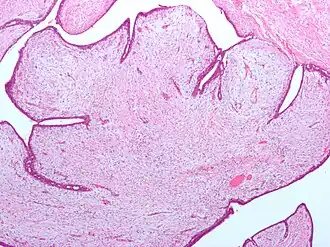

| Tumores filoides possuem grandes fendas e um estroma celular mixoide. Micrografia. Coloração H&E. | |